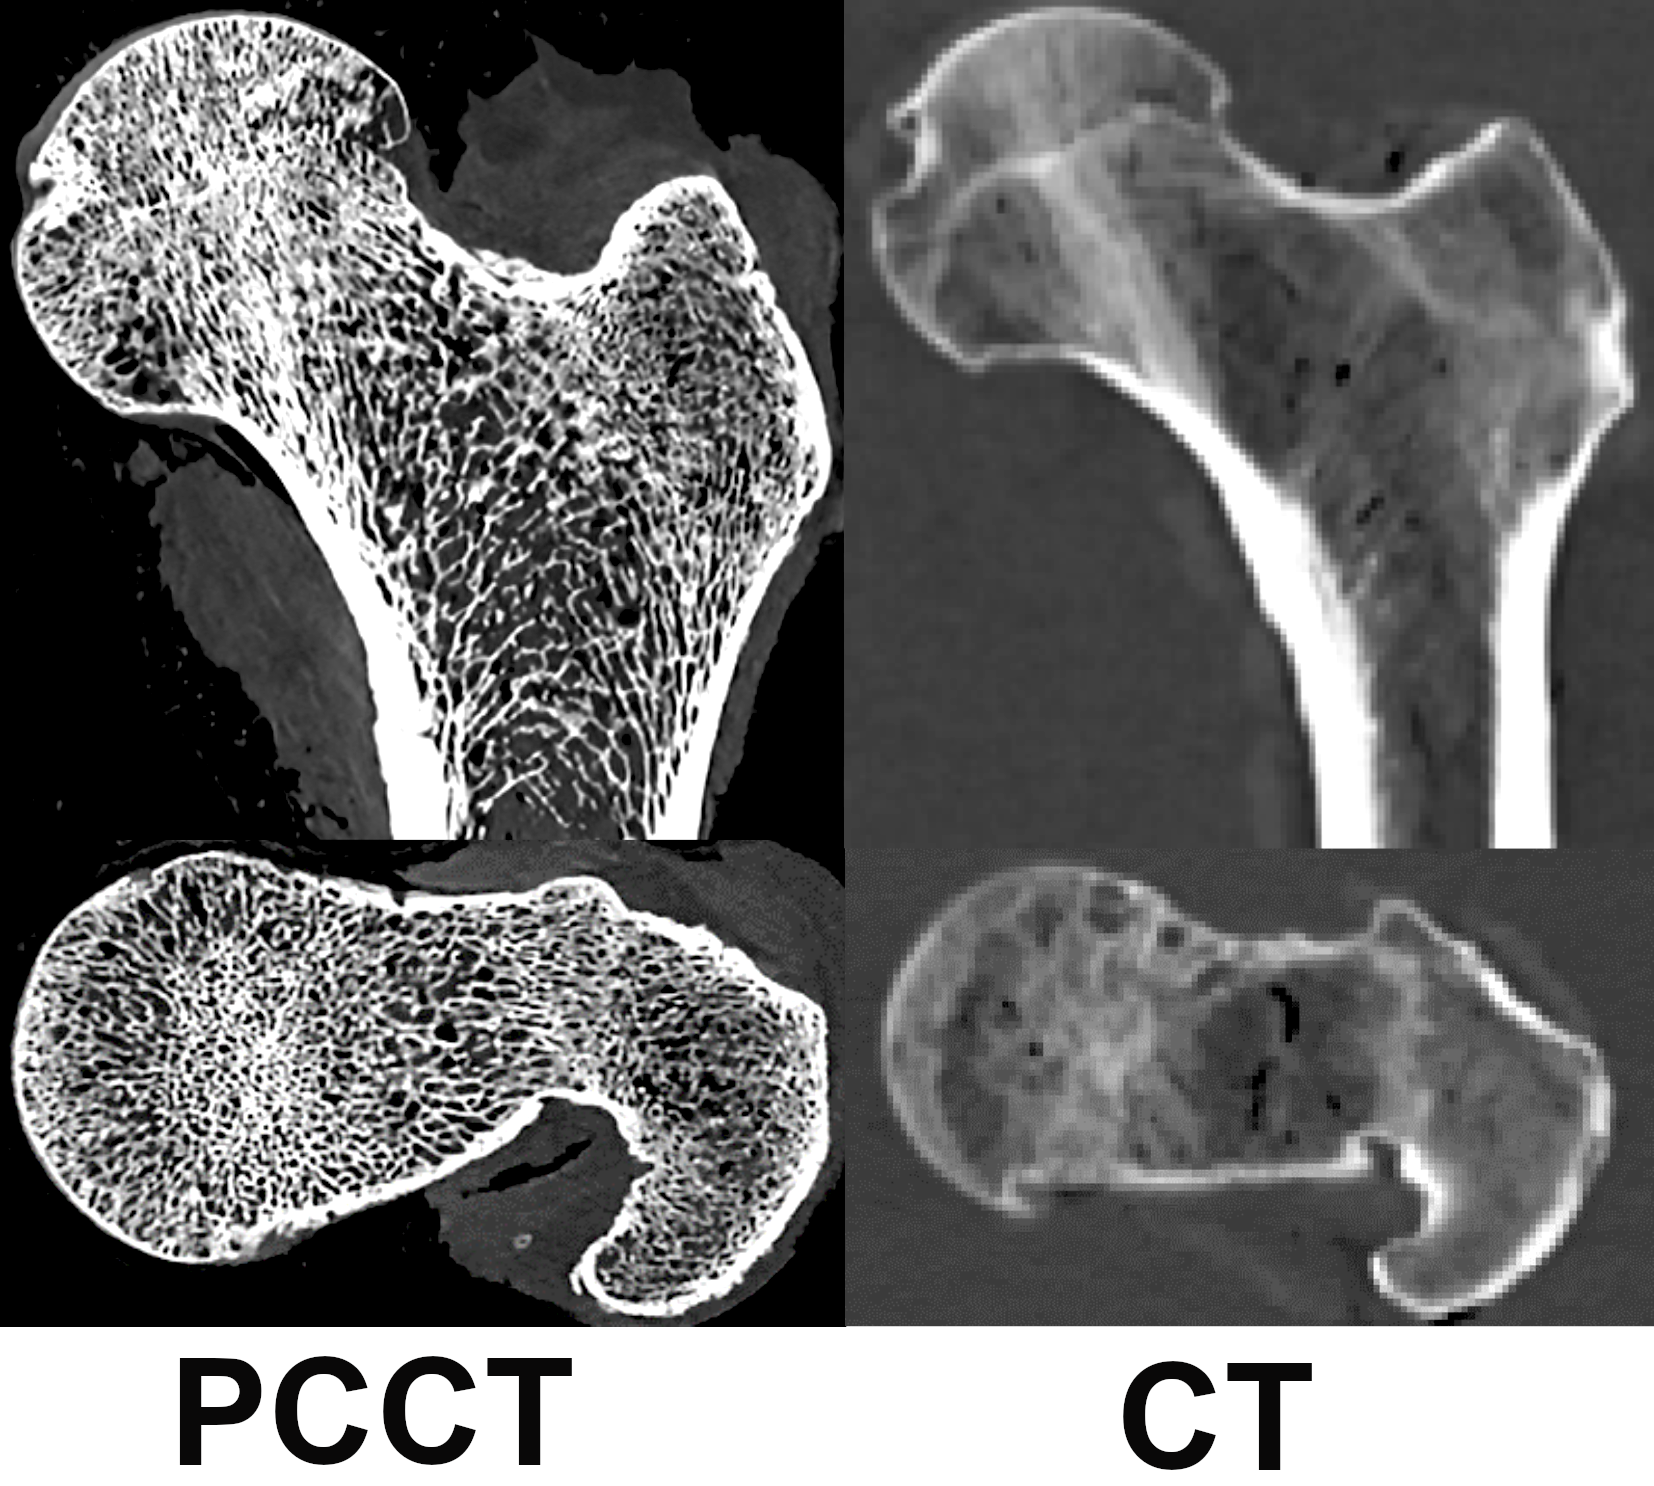

Advanced imaging techniques for assessing skeletal fragility

PCCT Image

Establishing methods for using photon-counting computed tomography (PCCT) evaluation of bone density and microstructure